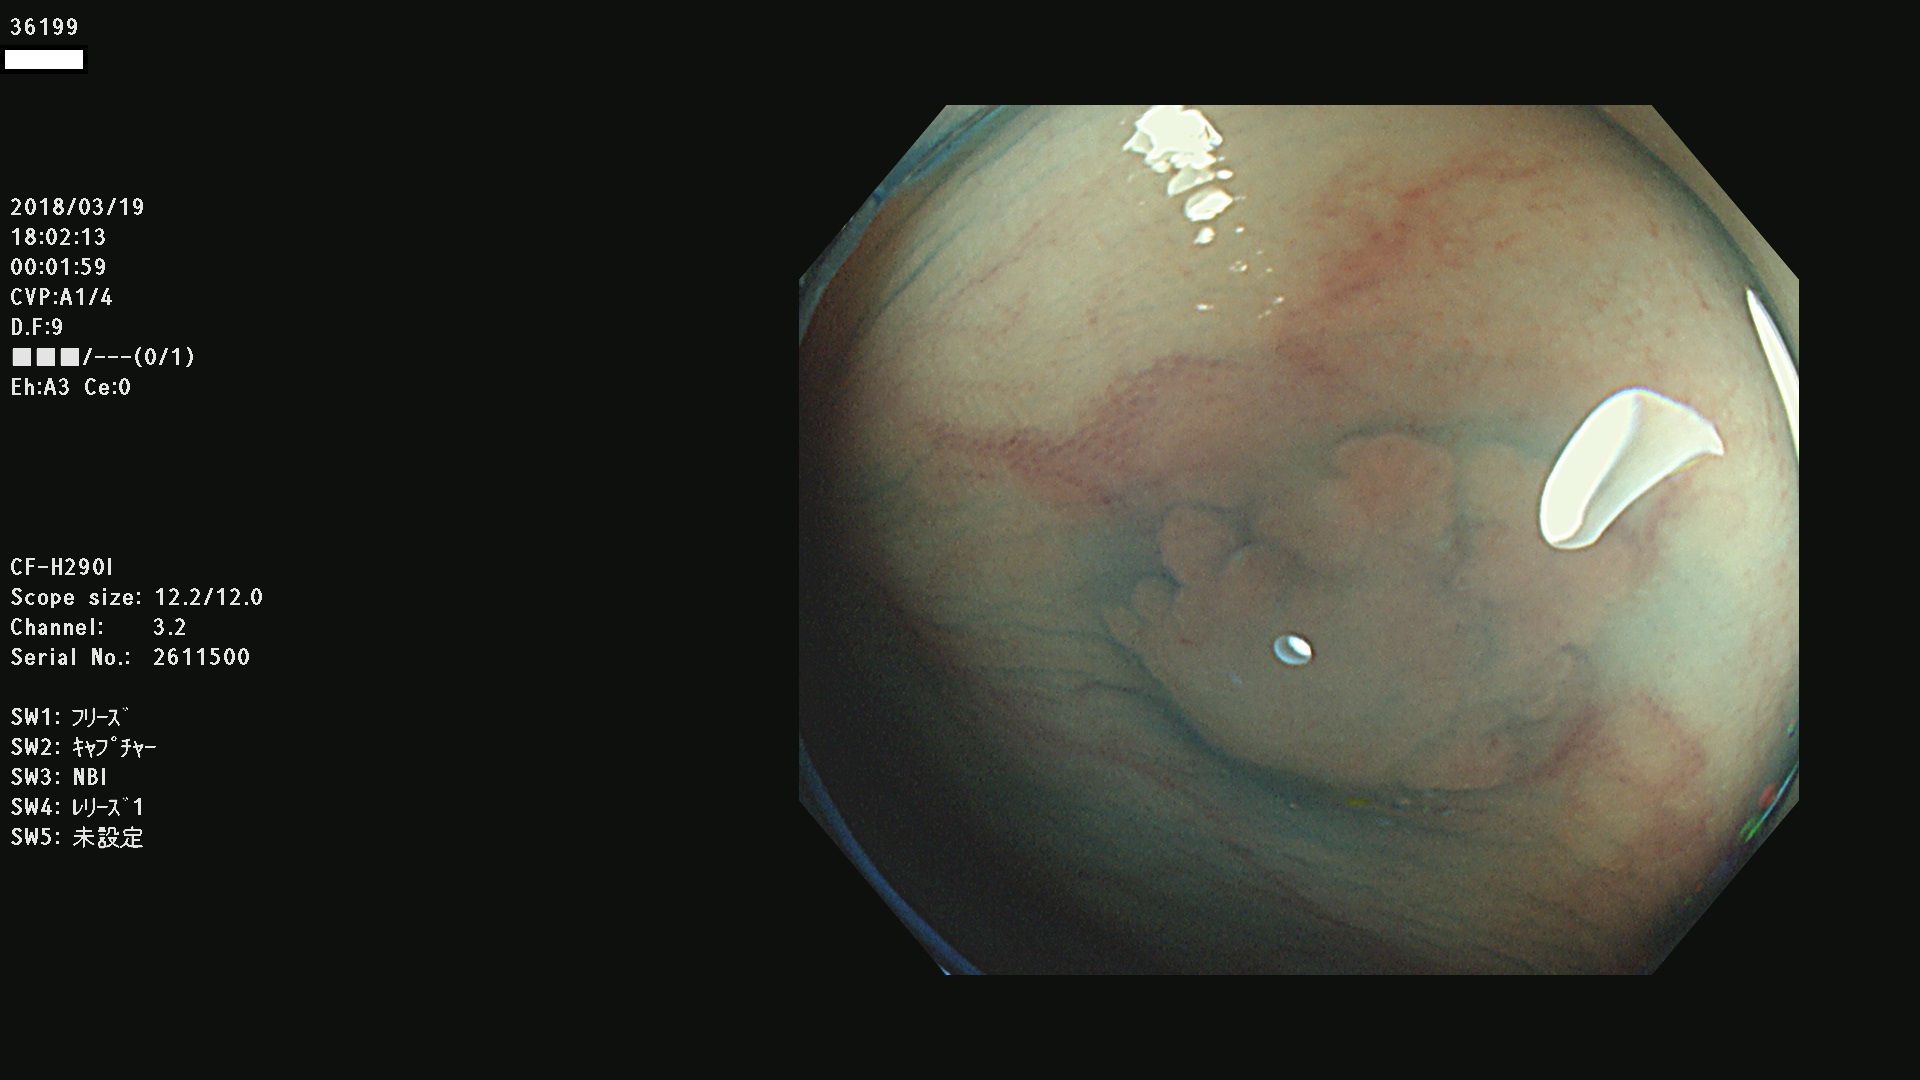

発見困難で危険性の高い平坦型病変(上記100名より抽出) ![]()